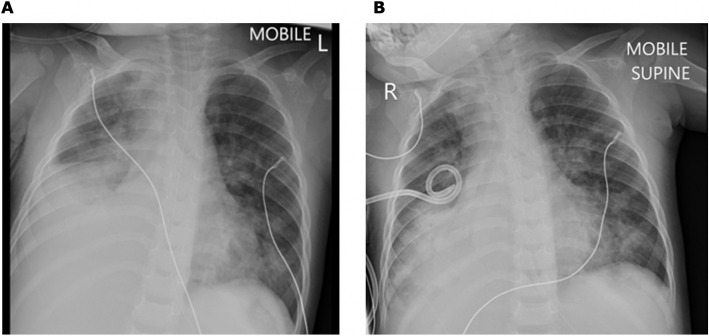

The child was assessed to have KD considering persistent fever, lymphadenopathy, desquamating rash, oral mucositis, extremity oedema, and BCG reactivation. This was complicated by MAS, as evidenced by hyperferritinaemia, hypertriglyceridaemia, pancytopenia, lethargy, and liver dysfunction. Chest radiograph and ultrasound demonstrated right parapneumonic pleural effusion, which was subsequently drained via pigtail thoracostomy drain (Fig. 6). Pleural fluid analysis demonstrated an exudate with lymphocyte predominance; HAdV was detected on pleural fluid PCR (Ct value 29.83); microscopy and culture were negative. Intravenous methylprednisolone was administered at 10 mg/kg once daily for three consecutive days, followed by prednisone 1 mg/kg/day orally, tapered over a week. The steroid pulse was followed by defervescence, normalising CRP trend, and gradual resolution of the cytopenias. She also received aspirin 5 mg/kg/day. Repeat echocardiography on day 14 of admission showed no coronary abnormalities.

Fig. 6.

Case 2, Chest radiographs on day 4 of admission. A Chest radiograph (anterior–posterior projection) showing right lower zone opacification with blunting of the costophrenic angle suggestive of right pleural effusion, with compression atelectasis of right middle lobe and right lower lobe; associated opacification in right upper lobe, left lingula, and left lower lobe. B Chest radiograph (anterior–posterior projection) showing right intercostal pigtail drain in situ with partial drainage of pleural effusion; associated dense residual homogeneous opacity in the right lower lobe and multilobar infiltrates involving the right middle lobe, left lingula, and left lower lobe